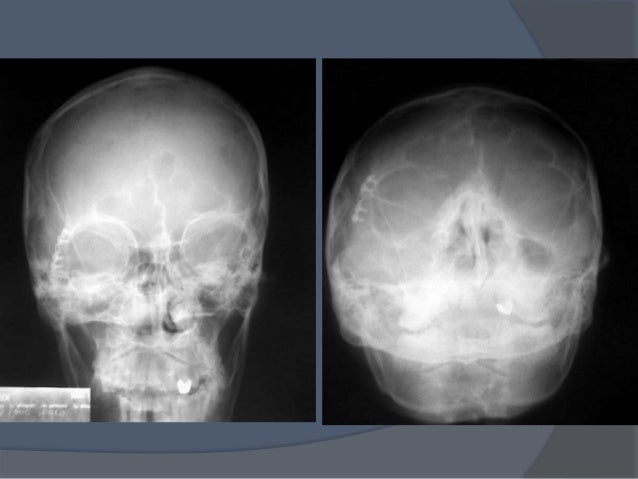

*En el caso de rx convencionales, tener una lateral, una de frente, para realizar la valoración de diferentes ángulos frecuente • Impacto lateral • Disminución volumen La mayoría de las veces el hueso malar se rota y la porción frontal de este se va hacia interior y eso hace que haya una disminución del continente.

Hueso malar El hueso cigomático (también conocido como el malar) es uno de los huesos formados más irregulares del cráneo Consta de tres procesos diferentes, variando en tamaño y forma Debido a que el par de ellos sobresalen lateralmente y forman las eminencias de la cara ( “pómulos “), ambos son propensos a fracturas. Radiografía que permite la evaluación de senos paranasales, junto a RX Caldwell y lateral de cráneo Se utiliza para confirmar sinusitis, delinear fracturas del hueso malar y, en general, para ver el macizo cráneo facial. También existen técnicas como la de Malar o Waters donde se utilizan posiciones intermedias (semiaxiales) Cuál es la característica que tienen que decir para determinar si esta Rx está bien o no?.

El hueso malar es normal bilateralmente Los senos maxilares se ven bien neumatizados El tabique nasal es central En los tejidos blandos no se ven masas, calcificaciones ni cuerpos extraños CONCLUSIÓN RX DE WATERS SIN HALLAZGOS PATOLÓGICOS DR Médico Radiólogo Rionegro, PACIENTE ESTUDIO RX COLUMNA LUMBOSACRA Radiodensidad ósea. So apoyo óseo (todo el apoyo es en hueso malar) y tener una disposición oblicua con respecto al plano oclusal, tienen una mayor tendencia a la flexión provocada por fuerzas horizontales, el soporte es siempre apical, en el malar, de ahí que se generen esos momentos de flexión que debemos minimizarLa primera precaución es quirúrgica. Huesos del cráneo Hueso frontal El hueso frontal (os frontale PNA) es un hueso del cráneo humano Es un hueso plano, impar, central, simétrico con 7 Páginas • 559 Visualizaciones Huesos Del Craneo HUESOS DEL CRÁNEO El cráneo es una caja ósea que contiene y protege al cerebro, el cerebelo, el tallo cerebral y los órganos de la.